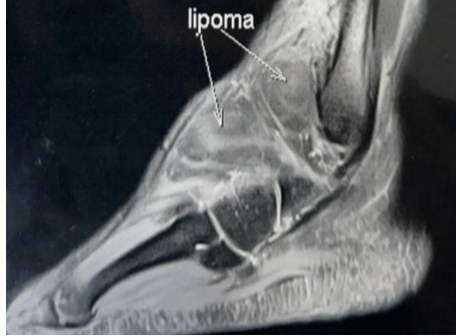

To confirm our diagnosis, we went for further investigation with an MRI to get an exact diagnosis and to rule out any soft-tissue malignancy. MRI of the right ankle revealed a well-encapsulated, homogeneously hyperintense lesion on both T1- and T2-weighted sequences, consistent with a lipoma (Fig. 2), located superficial to the anterior capsule and deep to the inferior extensor retinaculum. There was no intra-articular extension.

Figure 2: Lipomatous tissue over the anterolateral aspect of the ankle.

A calcaneonavicular coalition was identified, appearing as a fibro-osseous connection between the anterior process of the calcaneum and the lateral aspect of the navicular bone. Surgery was performed under spinal anesthesia with the patient in the supine position and a pneumatic tourniquet applied to the thigh. An anterolateral incision was made, centered over the swelling and extending from the lateral malleolus toward the sinus tarsi. The superficial peroneal nerve was identified early and carefully protected within the skin flap throughout the procedure. Dissection was carried out through the subcutaneous tissue and the deep fascia. The extensor digitorum brevis (EDB) muscle belly was encountered and divided to expose deeper structures. The inferior extensor retinaculum was incised longitudinally to improve visualization. A well-encapsulated, yellowish, lobulated mass was identified, adherent to the anterior capsule of the ankle joint but with no intra-articular extension. The capsule was preserved. The lesion, measuring almost 6 × 3 cm, was meticulously dissected off the capsule and adjacent tissues and excised en masse (Fig. 3 and 4).